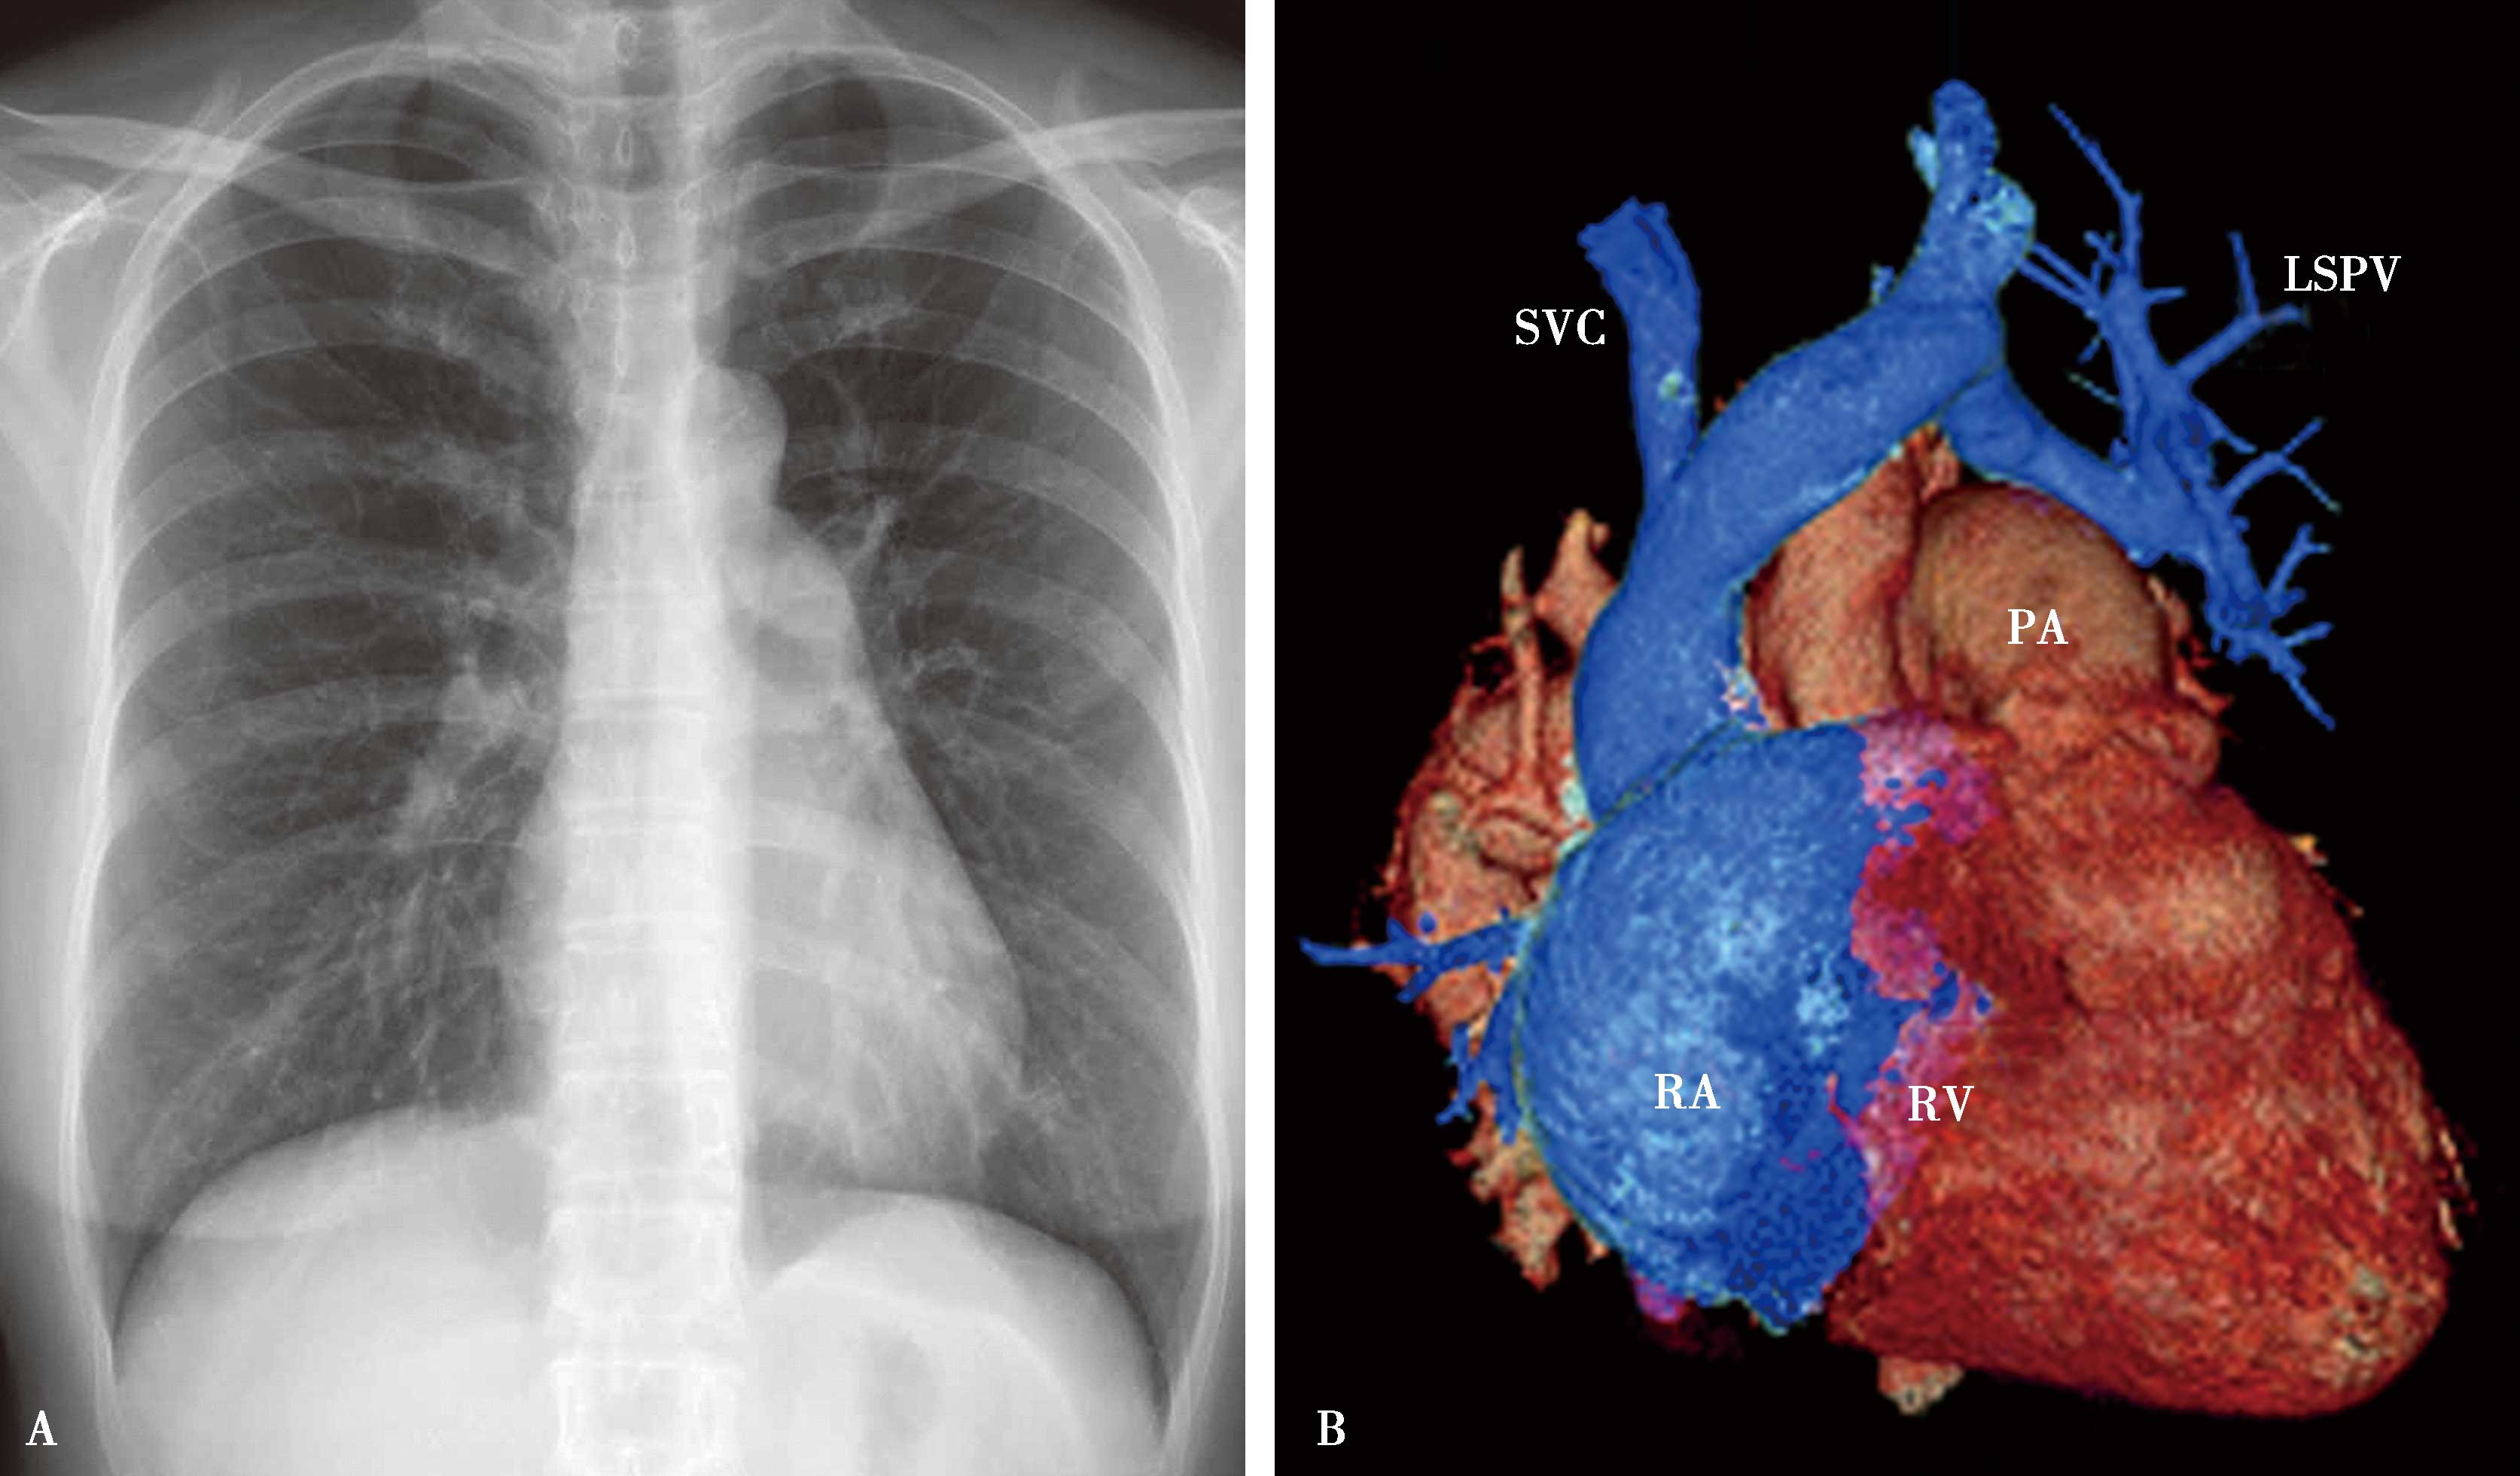

图7-2-1 女,29岁,心悸;超声心动图示:心内结构未见异常

X线片(A)示两肺血均匀增多,右心轻度增大;诊断为少-中等量左-右分流先天性心脏病,房水平可能性大。CTA(B)证实为部分性(心上型)肺静脉畸形引流。SVC:上腔静脉;LSPV:左上肺静脉;PA:主肺动脉;RA:右心房;RV:右心室